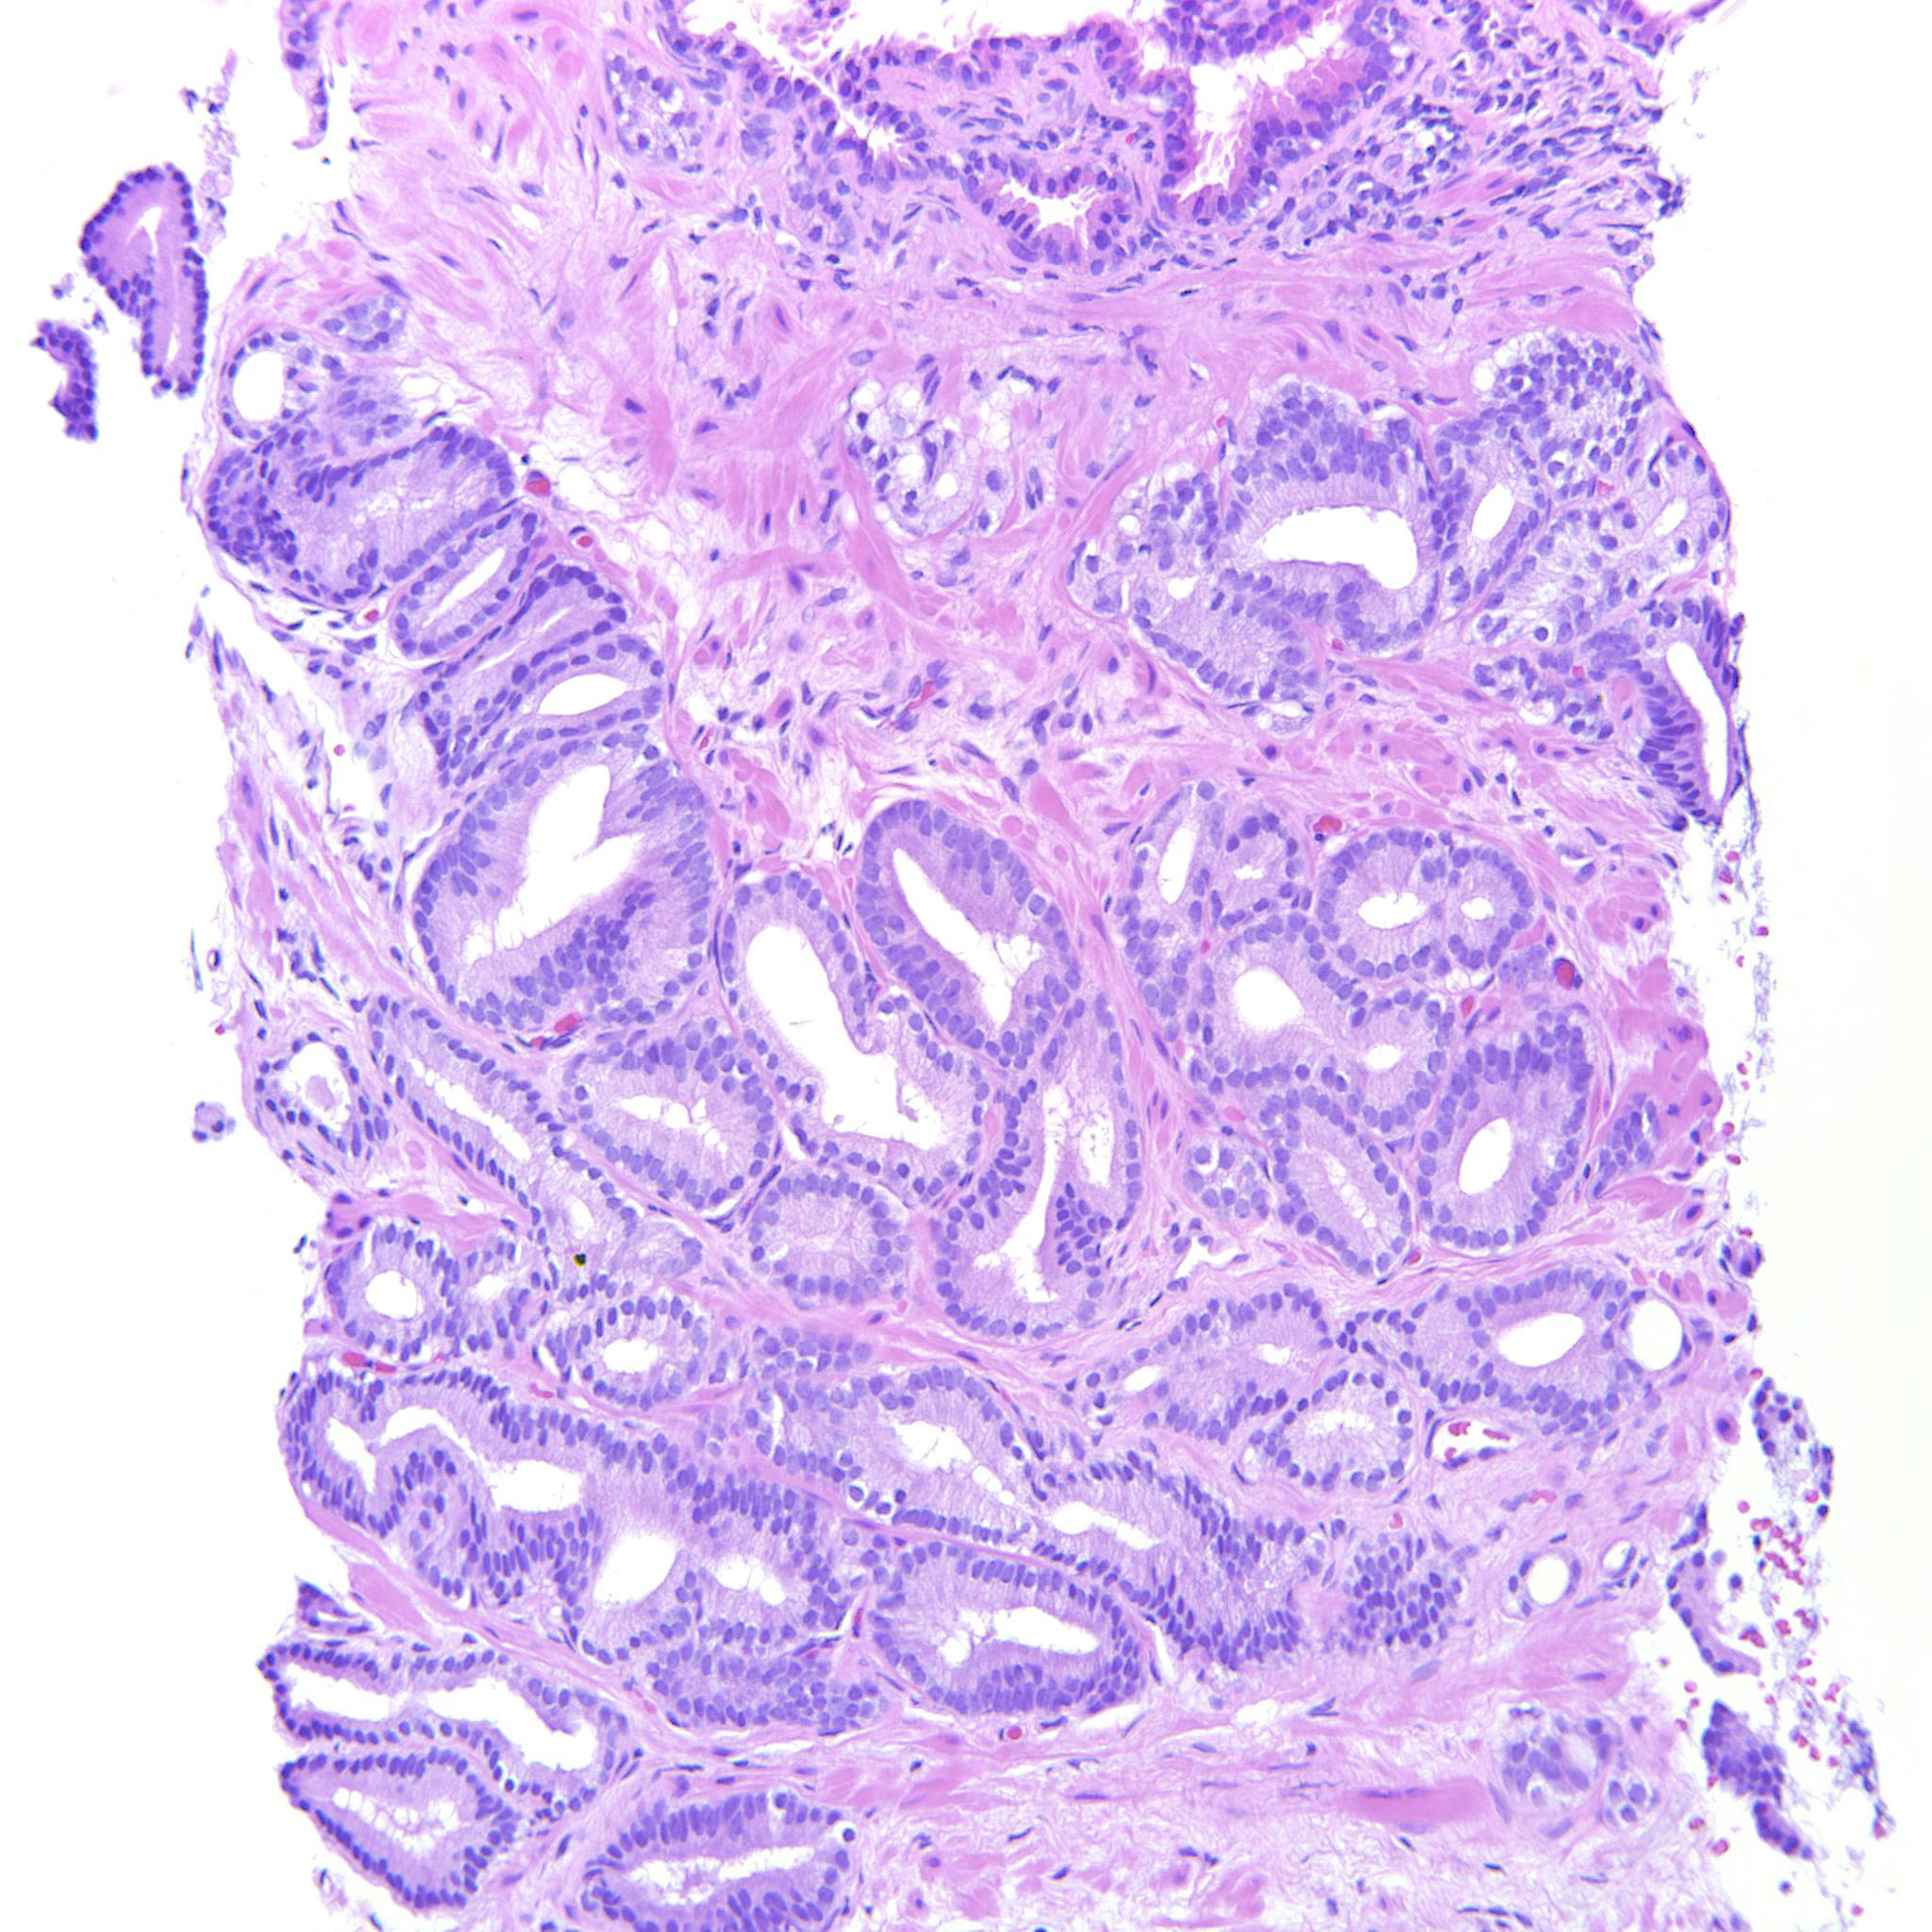

Consensus grade: GS 3+4=7 (ISUP 2)

Case description (by case creator):

A lot of the tumor is GP3 but there are also a couple of cribriform glands. The epithelium is tall columnar, sometimes with elongated nuclei but the tumor does not have other features of ductal adenocarcinoma and should probably be considered a variant of acinar adenocarcinoma of the prostate.